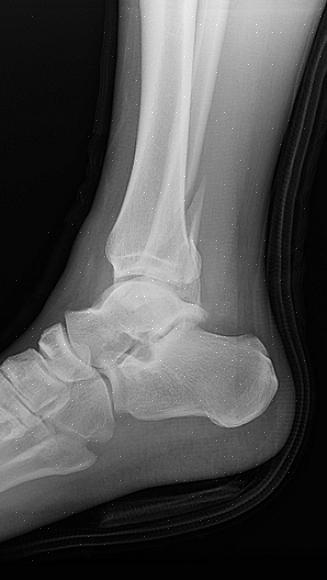

הרופא יתחיל את תהליך האבחון במגע ומישוש באזור. לאחר מכן, איש המקצוע הרפואי יבצע צילומי רנטגן של האזור הפגוע. מדי פעם, אם קיימת אפשרות ששברת את הקרסול, הרופא שלך יבצע בדיקת CT על מנת להעריך את מידת הפציעה שלך.